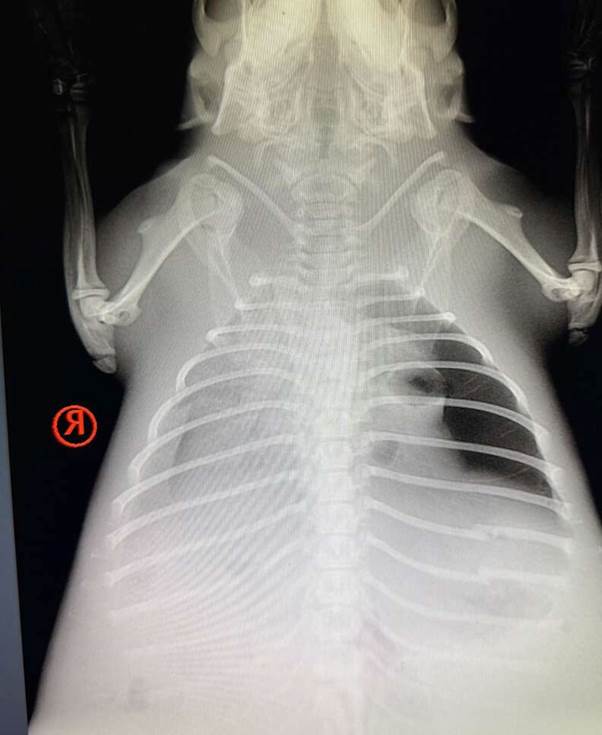

At BRWC, the veterinary team quickly assessed the little patient. What they found was heartbreaking. The beaver, likely only a year old, was suffering from severe pneumonia and possible internal trauma.

“On admission, our veterinary team noted that she was weak with labored breathing,” the center shared on Facebook. “X-rays indicated pneumonia or fluid from near-drowning, as well as trauma on the left side.”

The possibility of near-drowning, coupled with the injuries, suggested she had been through a harrowing ordeal — perhaps washed out of her family’s dam during flooding, or caught in a collapse. Whatever had happened, the young beaver’s survival now depended entirely on the dedicated team at BRWC.